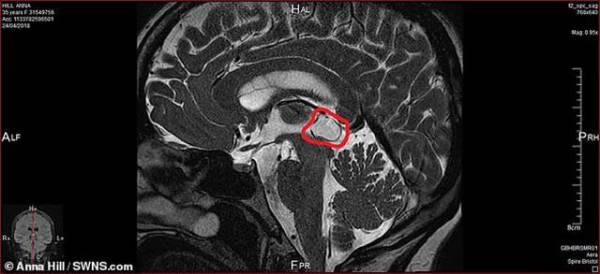

Vào đầu năm nay, Anna buộc phải tạm nghỉ công việc của mình. Cô quyết định khám tại một bệnh viện tư nhân, tại đây các bác sĩ đã làm các loại xét nghiệm não và phát hiện ra một khối u sâu 1.8 cm.